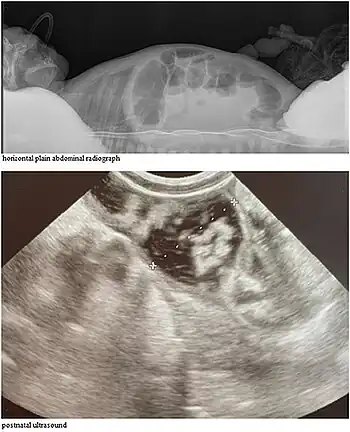

CCD may be detectable on prenatal ultrasound.[4][5]

After birth, signs in affected babies typically are abdominal distension, visible peristalsis, and watery stools persistent from birth that show chloride loss of more than 90 mmol/L.[5]

CCD causes persistent secretory diarrhea. In a fetus, it leads to polyhydramnios and premature birth. Immediately after birth, it leads to dehydration, hypoelectrolytemia, hyperbilirubinemia, abdominal distention, and failure to thrive.[3]